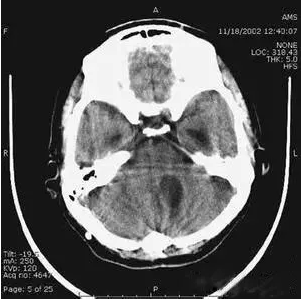

6、部分容積效應(yīng)產(chǎn)生的偽影及對策

部分容積效應(yīng)偽影的形狀可因物體的不同而不一樣,一般在重建后橫斷面圖像上可見條形、環(huán)形或大片干擾的偽像。最常見和典型的現(xiàn)象是在頭顱橫斷面時的顳部出現(xiàn)的條狀偽影,又稱哼氏偽影。該偽影現(xiàn)象可采用薄層掃描而減弱;在西門子系列的CT機中.用VAR掃描技術(shù)可抑制該偽影。